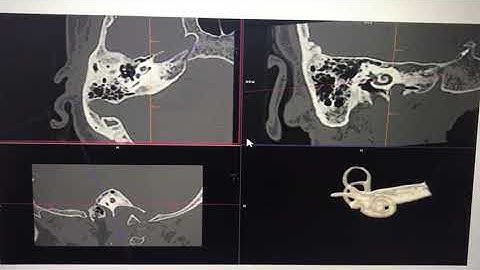

How to Create 3D Cochlea in CT Scan | Complete Post-Processing Tutorial #medicos1k86 #radiology #ct